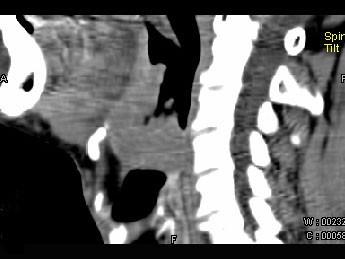

问题 男,74岁,咽喉部不适一年余,近两三个月咽喉疼痛,吞咽困难,CT如图所示,最可能诊断是()

选项 A.喉癌 B.会厌癌 C.声带癌 D.声门下区癌 E.跨声门型癌

答案 B